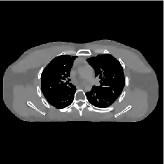

This section compares the generalization capabilities between the proposed MBIR method, PWLS-ST-, and a denoising deep NN, FBPConvNet [14], that are trained from the phantom data; in particular, we tested the trained PWLS-ST- and FBPConvNet models to phantom and clinical scan data. The results in Fig. 6 show that the non-MBIR FBPConvNet method has higher overfitting risks, compared to the proposed PWLS-ST- MBIR method. When tested on clinical scan data, PWLS-ST- achieves much more accurate reconstruction, compared to FBPConvNet. See Fig. 6(b). When tested on phantom data, FBPConvNet generates more unnatural features as the number of views reduces, although it gives lower RMSE values compared to PWLS-ST-. See zoom-ins in Fig. 6(a). The FBPConvNet results above correspond to those in the recent work [16] that FBPConvNet [14] generated some unexpected structures.